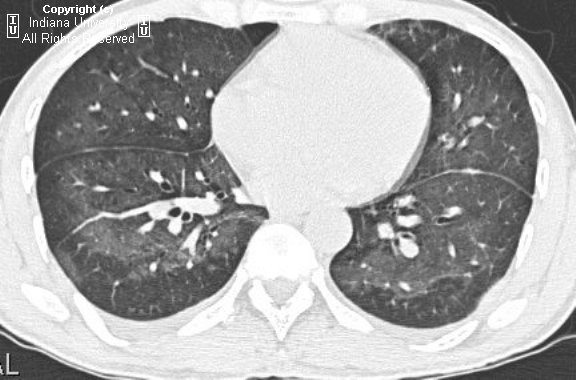

PCP pneumonia

• CXR - usually normal; may see subtle groundglass opacities

• HRCT

• Diffuse, symmetric ground-glass opacities are the dominant finding. There may be sparing of the subpleural lung in ~40% of the cases.

• Thin walled cysts in the same distribution as the ground-glass opacities may be seen sometimes. These predispose the patient to pneumothorax.

• Adenopathy and pleural effusions are rare. Consider other diagnoses in this case.